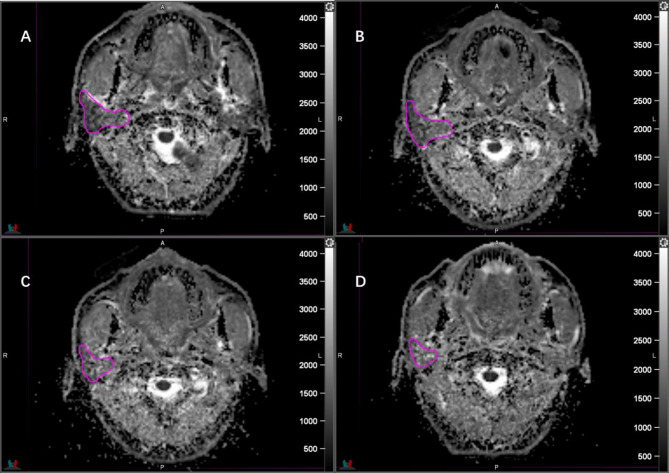

Methods: Nasopharyngeal carcinoma patients receiving definitive chemoradiotherapy were prospectively enrolled. Magnetic Resonance Diffusion-Weighted Imaging (MR-DWI) was performed at pre-radiotherapy (pre-RT), the 5th, 15th fractions, and end of radiotherapy. ADC values and volumes for ipsilateral (IP) and contralateral parotid glands (CP) were recorded. Salivary function was assessed using scintigraphy (SGS) and the Radiation Therapy Oncology Group (RTOG) xerostomia criteria.

Abstract Image